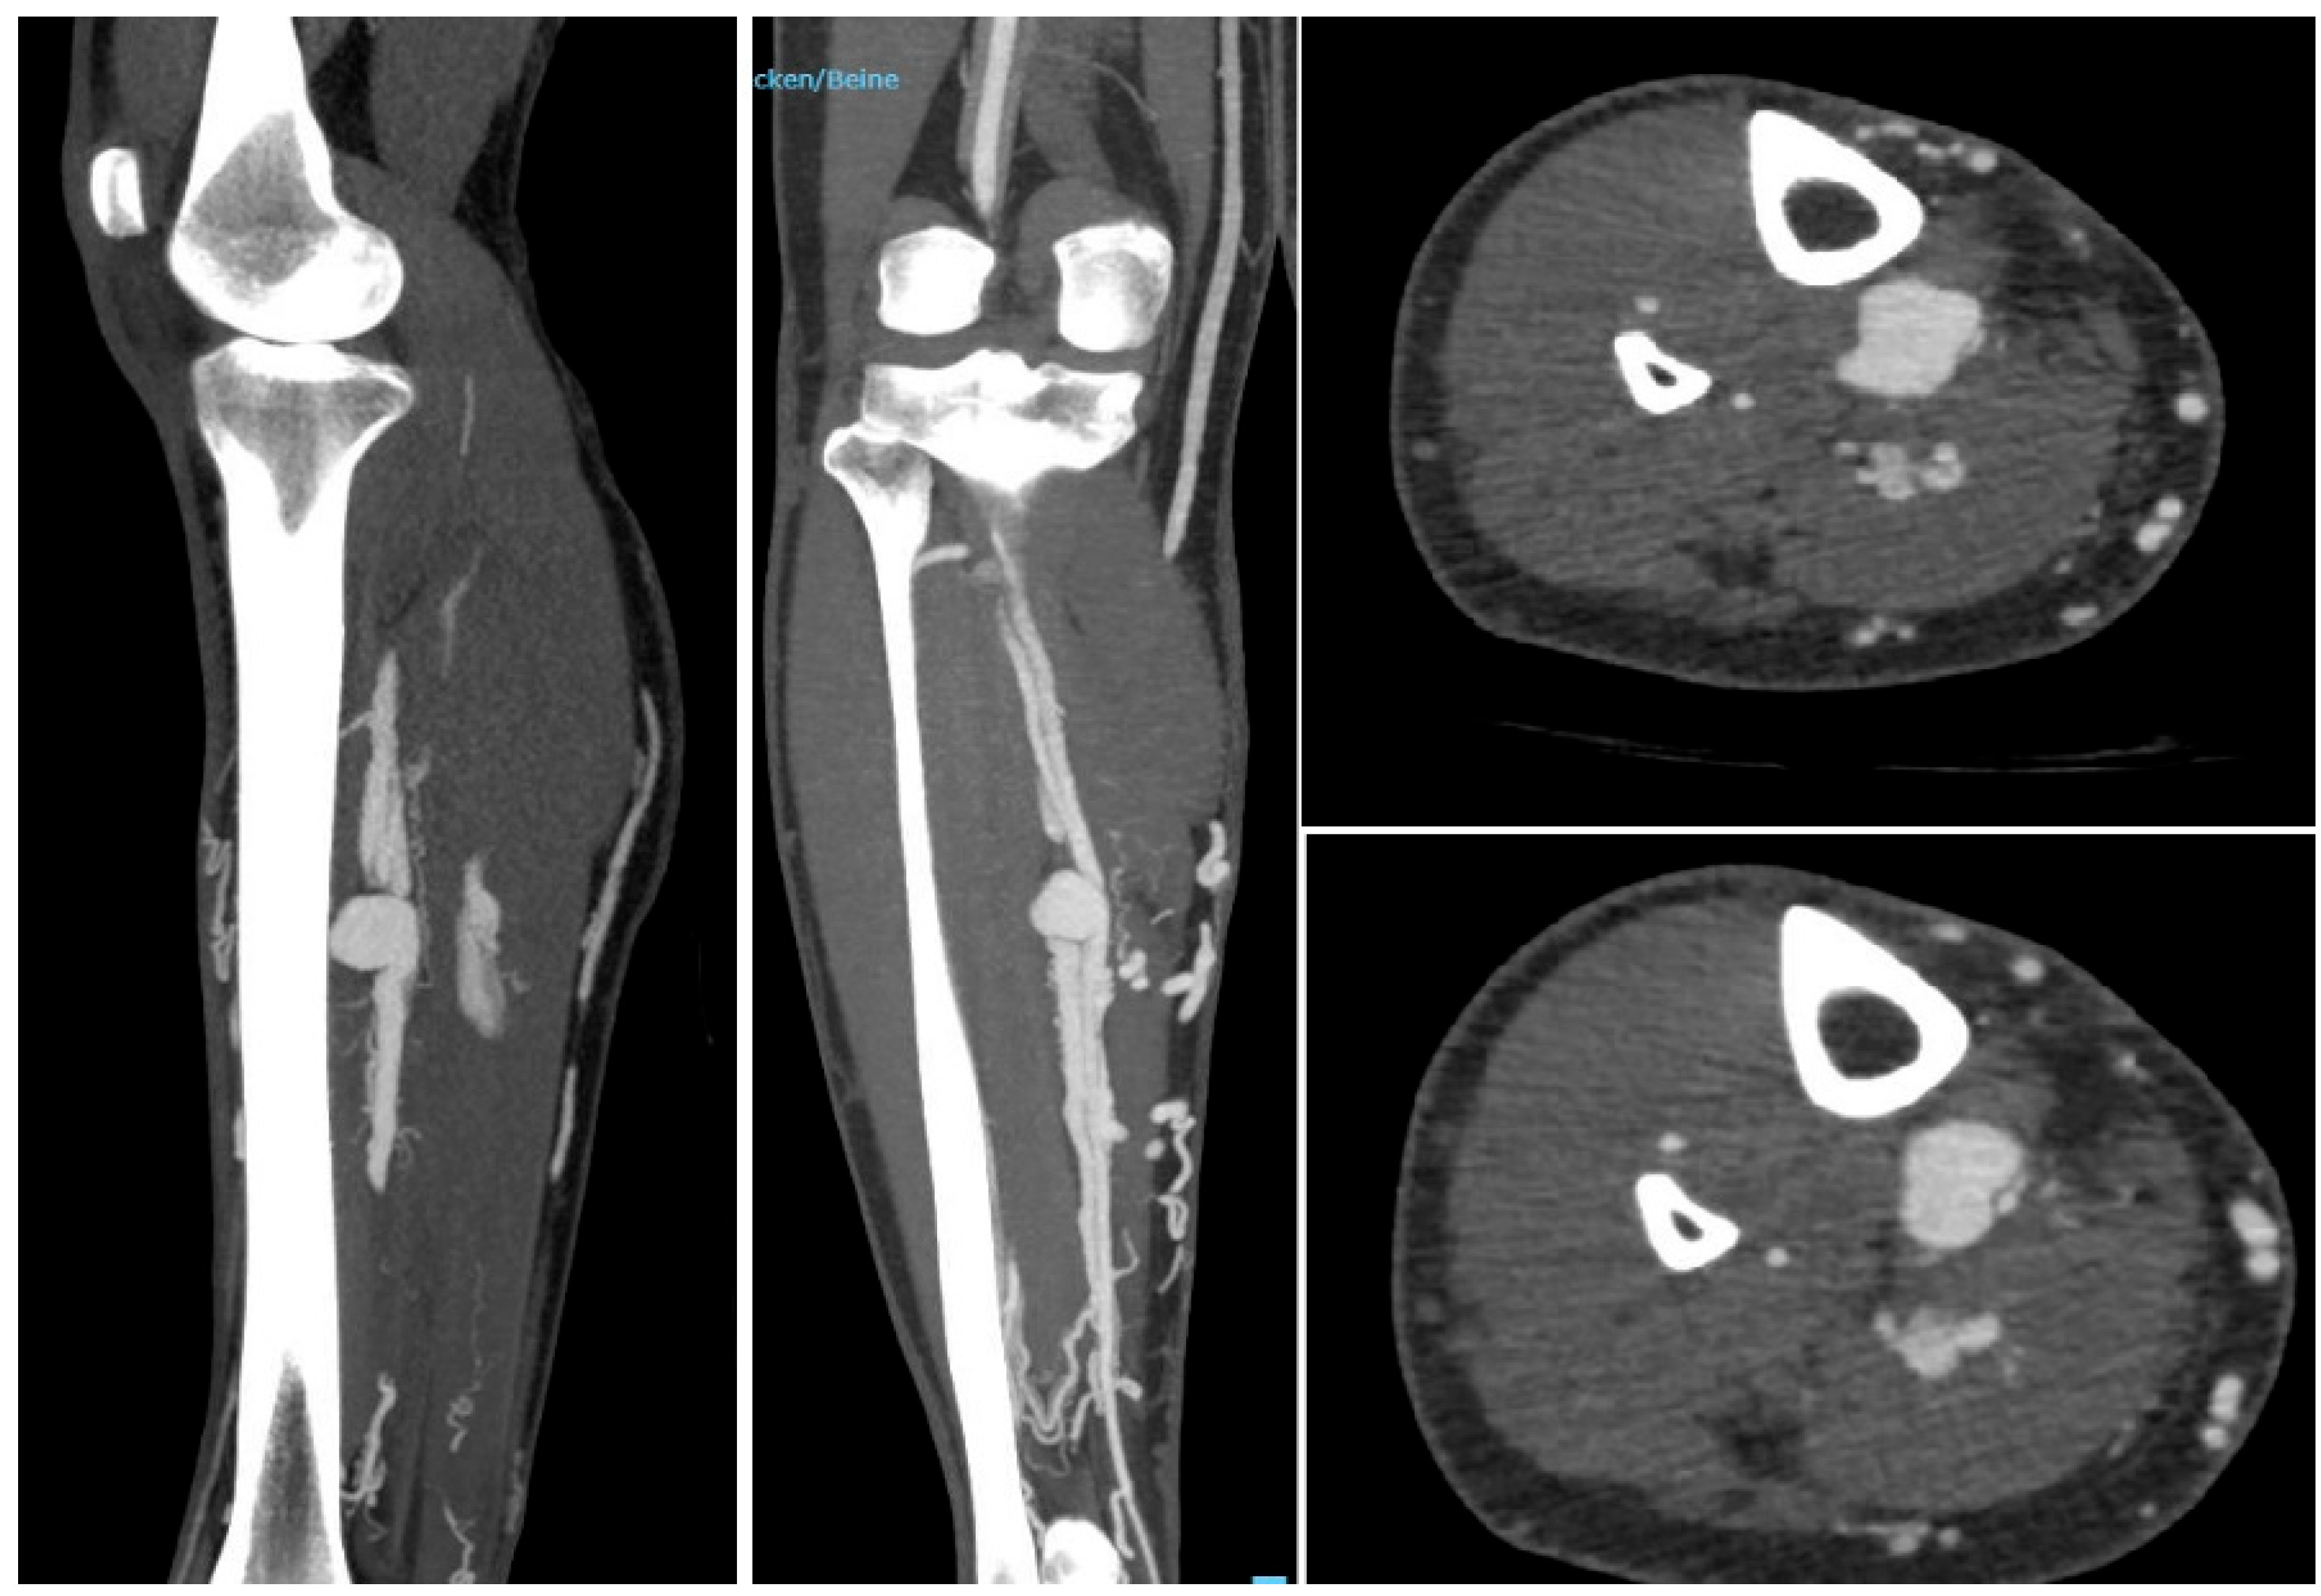

- Chrencik, M. T. et al. Infrapopliteal Arterial Pseudoaneurysm Development Secondary to Blunt Trauma: Case Series and Literature Review Vasc endovascular surg 2020 vol. 54 (4) 367-374.

- Brunoro M. et al. Endovascular Treatment of an Anterior Tibial Artery Pseudoaneurysm Secondary to Penetrating Trauma in a Young Patient: Case Report and Literature Review 2019 Ann Vasc Surg Volume 60, 479.e5-479.e9.

- Gratl A. et al., Treatment options of crural pseudoaneurysms Vasa 2014; 43: 209 – 215.

- Yamamoto Y. Et al. Endovascular coil embolization of a large tibioperoneal trunk pseudoaneurysm. Journal of Vascular Surgery Cases and Innovative Techniques 2020; Volume 6 number 3.